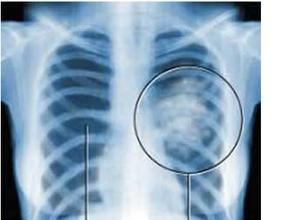

X線胸片、體層攝影、支氣管造影、CT掃描等檢查對於顯示和分析肺部良性腫瘤的特徵具有較高的診斷價值,最後確切診斷依靠病理組織學檢查。治療